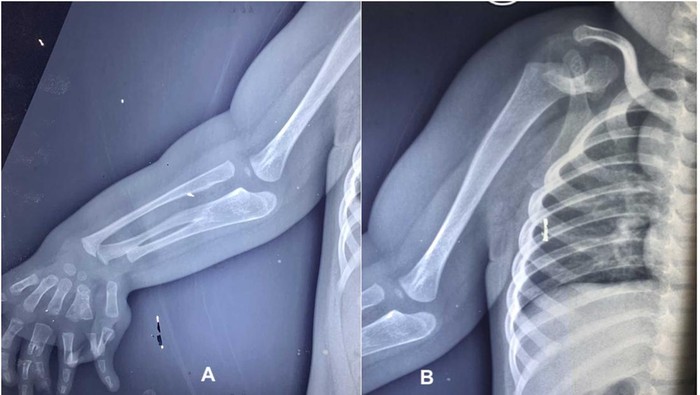

Seorang anak laki-laki berusia dua tahun di India, terlahir dengan kondisi langka anomali kongenital (congenital anomalies) yang membuat dirinya mengalami tiga lengan bawah dan duplikasi jari. Kasusnya ini diterbitkan dalam jurnal PlumX Metrics pada 2024, dengan judul ‘Congenital three-bone forearm – A rare disorder’.

Selain itu, rontgen tangan menunjukkan duplikasi tipe III pada jari tengah, duplikasi tipe V pada jari manis, jari kelingking yang mengalami deviasi ulnar, serta pergelangan tangan dengan tiga tulang. Sementara itu, anggota gerak atas kiri, wajah, tulang belakang, panggul, dan ekstremitas bawah tampak normal. Pasien tidak mengalami obesitas, dan hasil parameter darah berada dalam batas normal.Foto: jurnal PlumX Metrics

Berdasarkan hasil pemeriksaan, terlihat adanya pengecilan otot yang nyata di sekitar bahu dan skapula, disertai tidak adanya gerakan aktif pada abduksi, fleksi, maupun rotasi bahu. Siku dalam posisi fleksi 30 derajat tanpa kemampuan melakukan supinasi maupun pronasi. Lengan bawah dan pergelangan tangan tampak melebar.